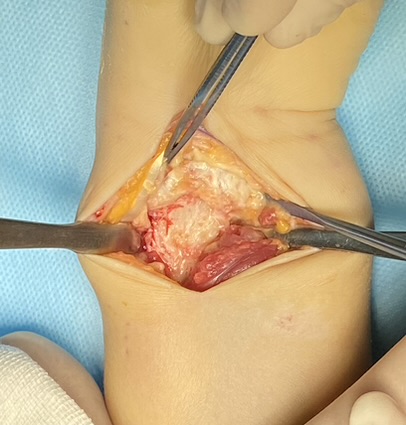

Клинический случай: внутрисуставной перелом дистального метаэпифиза лучевой кости — операция (остеосинтез пластиной)

Этап остеосинтеза: доступ, фиксация и контроль положения пластины.